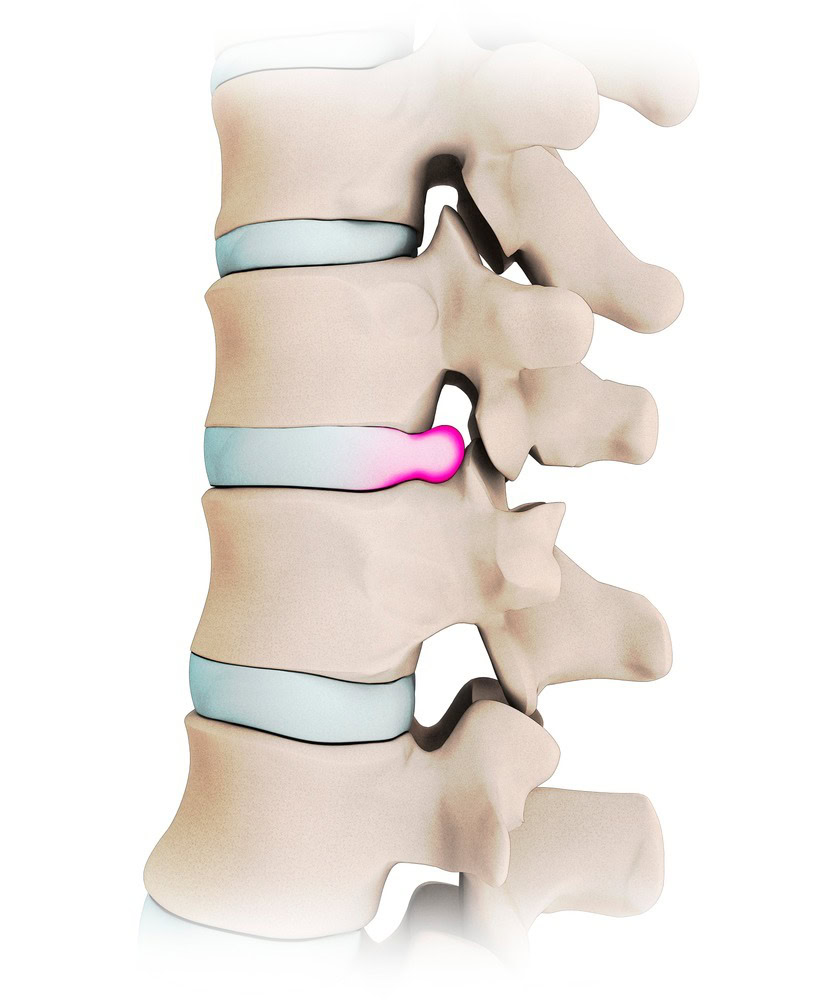

허리 디스크나 척추관 협착증이 있을 때 가장 대표적으로 시행되는 척추 주사입니다. 척추신경 바깥에 약물을 투여합니다.

1. 척추질환 발생

2. 염증물질 신경압박